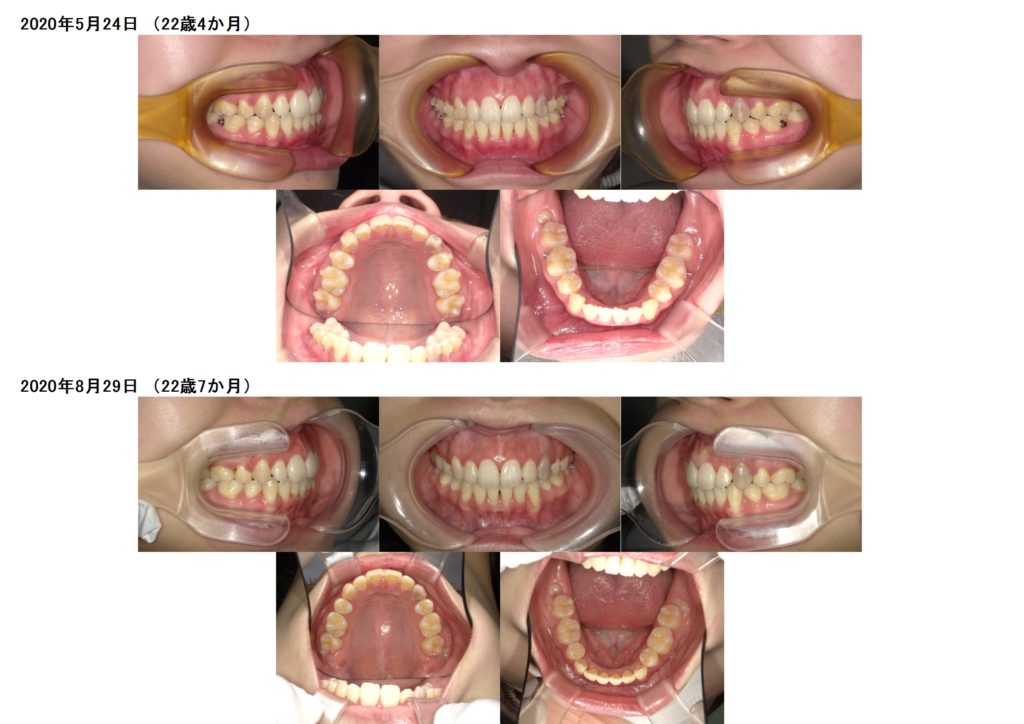

抜歯の治療例の写真

↑上下4番目の歯を左右抜歯し、約半年間側面にブラケットを装着しました。

↑抜歯、突出ケースでもしっかりとマウスピースを使うとこんなに早く変化が分かります。ここから再度噛み合わせの微調整に入るためのマウスピースを作成します。